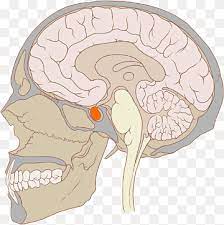

La diabetes insípida central es una enfermedad poco común que se origina por una deficiencia en la vasopresina, también conocida como hormona antidiurética, que es secretada por la glándula pituitaria posterior. Esta hormona es crucial para la regulación del equilibrio hídrico del organismo, ya que actúa en los riñones para promover la reabsorción de agua, reduciendo así la producción de orina.

En términos generales, la diabetes insípida se clasifica en dos tipos principales: central y nefrogénica. La forma central, que es el enfoque de esta explicación, representa aproximadamente un tercio de todos los casos de diabetes insípida. Dentro de esta categoría, la diabetes insípida central primaria se presenta sin una lesión identificable en las imágenes por resonancia magnética del hipotálamo y la glándula pituitaria. Este tipo de diabetes insípida puede ser idiopático, lo que significa que la causa es desconocida, o puede ser resultado de un proceso autoinmune que ataca las células del hipotálamo que producen vasopresina.

La diabetes insípida central secundaria es un trastorno que se produce como consecuencia de un daño en el hipotálamo o en el tallo pituitario. Este daño puede ser causado por una variedad de factores, incluyendo tumores, hipofisitis, infartos, hemorragias, encefalopatía anóxica, lesiones traumáticas en el cerebro o cirugías que involucren estas estructuras. La etiología de esta forma de diabetes insípida es diversa y puede incluir tanto causas benignas como malignas.

La resonancia magnética (RM) es una herramienta valiosa en el diagnóstico de la diabetes insípida, particularmente en la diferenciación entre diabetes insípida central y otras formas de poliuria. En la imagen ponderada por T1, la glándula pituitaria posterior normalmente presenta un «punto brillante» característico, que corresponde a la acumulación de arginina vasopresina. Sin embargo, en los casos de diabetes insípida central, este punto brillante es indetectable o se presenta de manera notablemente reducida. Esta disminución en la señal es un indicador importante de la disfunción en la producción o liberación de vasopresina.

Por el contrario, en la polidipsia primaria y en la diabetes insípida nefrogénica, el «punto brillante» en la pituitaria posterior suele estar presente y en un estado normal. Esto se debe a que en estas condiciones, la producción de vasopresina no está comprometida, lo que permite la visualización del punto brillante en la imagen de resonancia magnética.

Además de ayudar en la identificación de la diabetes insípida central, la resonancia magnética también puede detectar patologías subyacentes responsables de esta condición. Por ejemplo, tumores, lesiones o inflamaciones en la región del hipotálamo o la glándula pituitaria que pueden interferir con la producción de vasopresina.